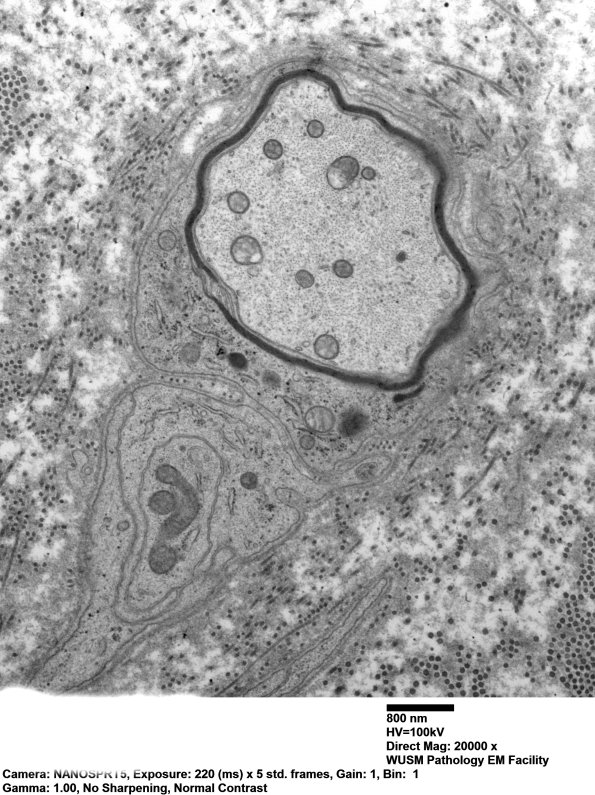

Two other examples of demyelinated axons in this case. (electron micrographs)